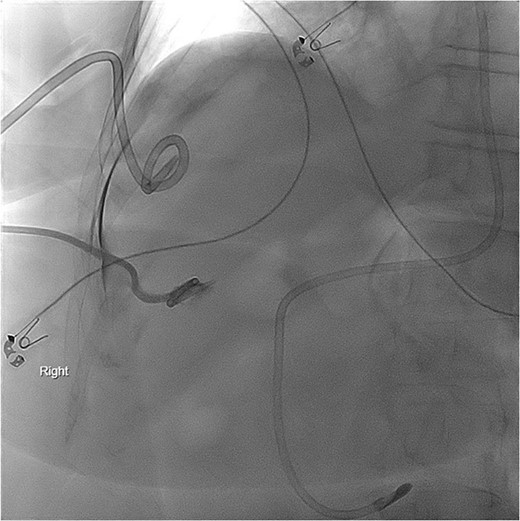

She was managed with bowel rest, parenteral nutrition, and octreotide. PCT output decreased but remained chylous throughout the hospitalization. Subsequent cholangiogram and PCT check revealed no fistulous connection to the thoracic cavity or lymphatic system (Fig. 5). Her hospitalization was further complicated by persistent distributive shock, adrenal insufficiency, and continued chyle leak. Though she was successfully extubated, her clinical status continued to decline. Per the wishes of the patient and family, she was transitioned to inpatient hospice and died shortly after.

PCT check using fluoroscopy showing the pigtail portion of the cholecystostomy tube within the gallbladder lumen as well as some leakage into the perihepatic space. No opacification of the pleural space.